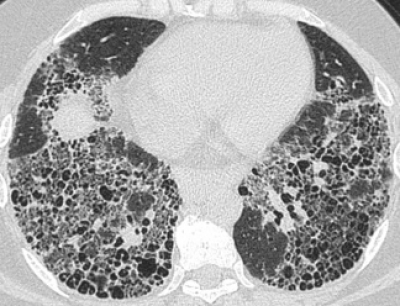

Ciudad de México. En el marco del Mes Mundial de la Fibrosis Pulmonar Idiopática (FPI), que se conmemora en septiembre, Boehringer Ingelheim lanzó su campaña internacional “La postal más importante que escribí”, con el fin de no solo dar visibilidad a esta enfermedad poco frecuente, sino también voz a quienes la padecen para que cuenten con un diagnóstico oportuno y un tratamiento correcto que mejore su calidad de vida.